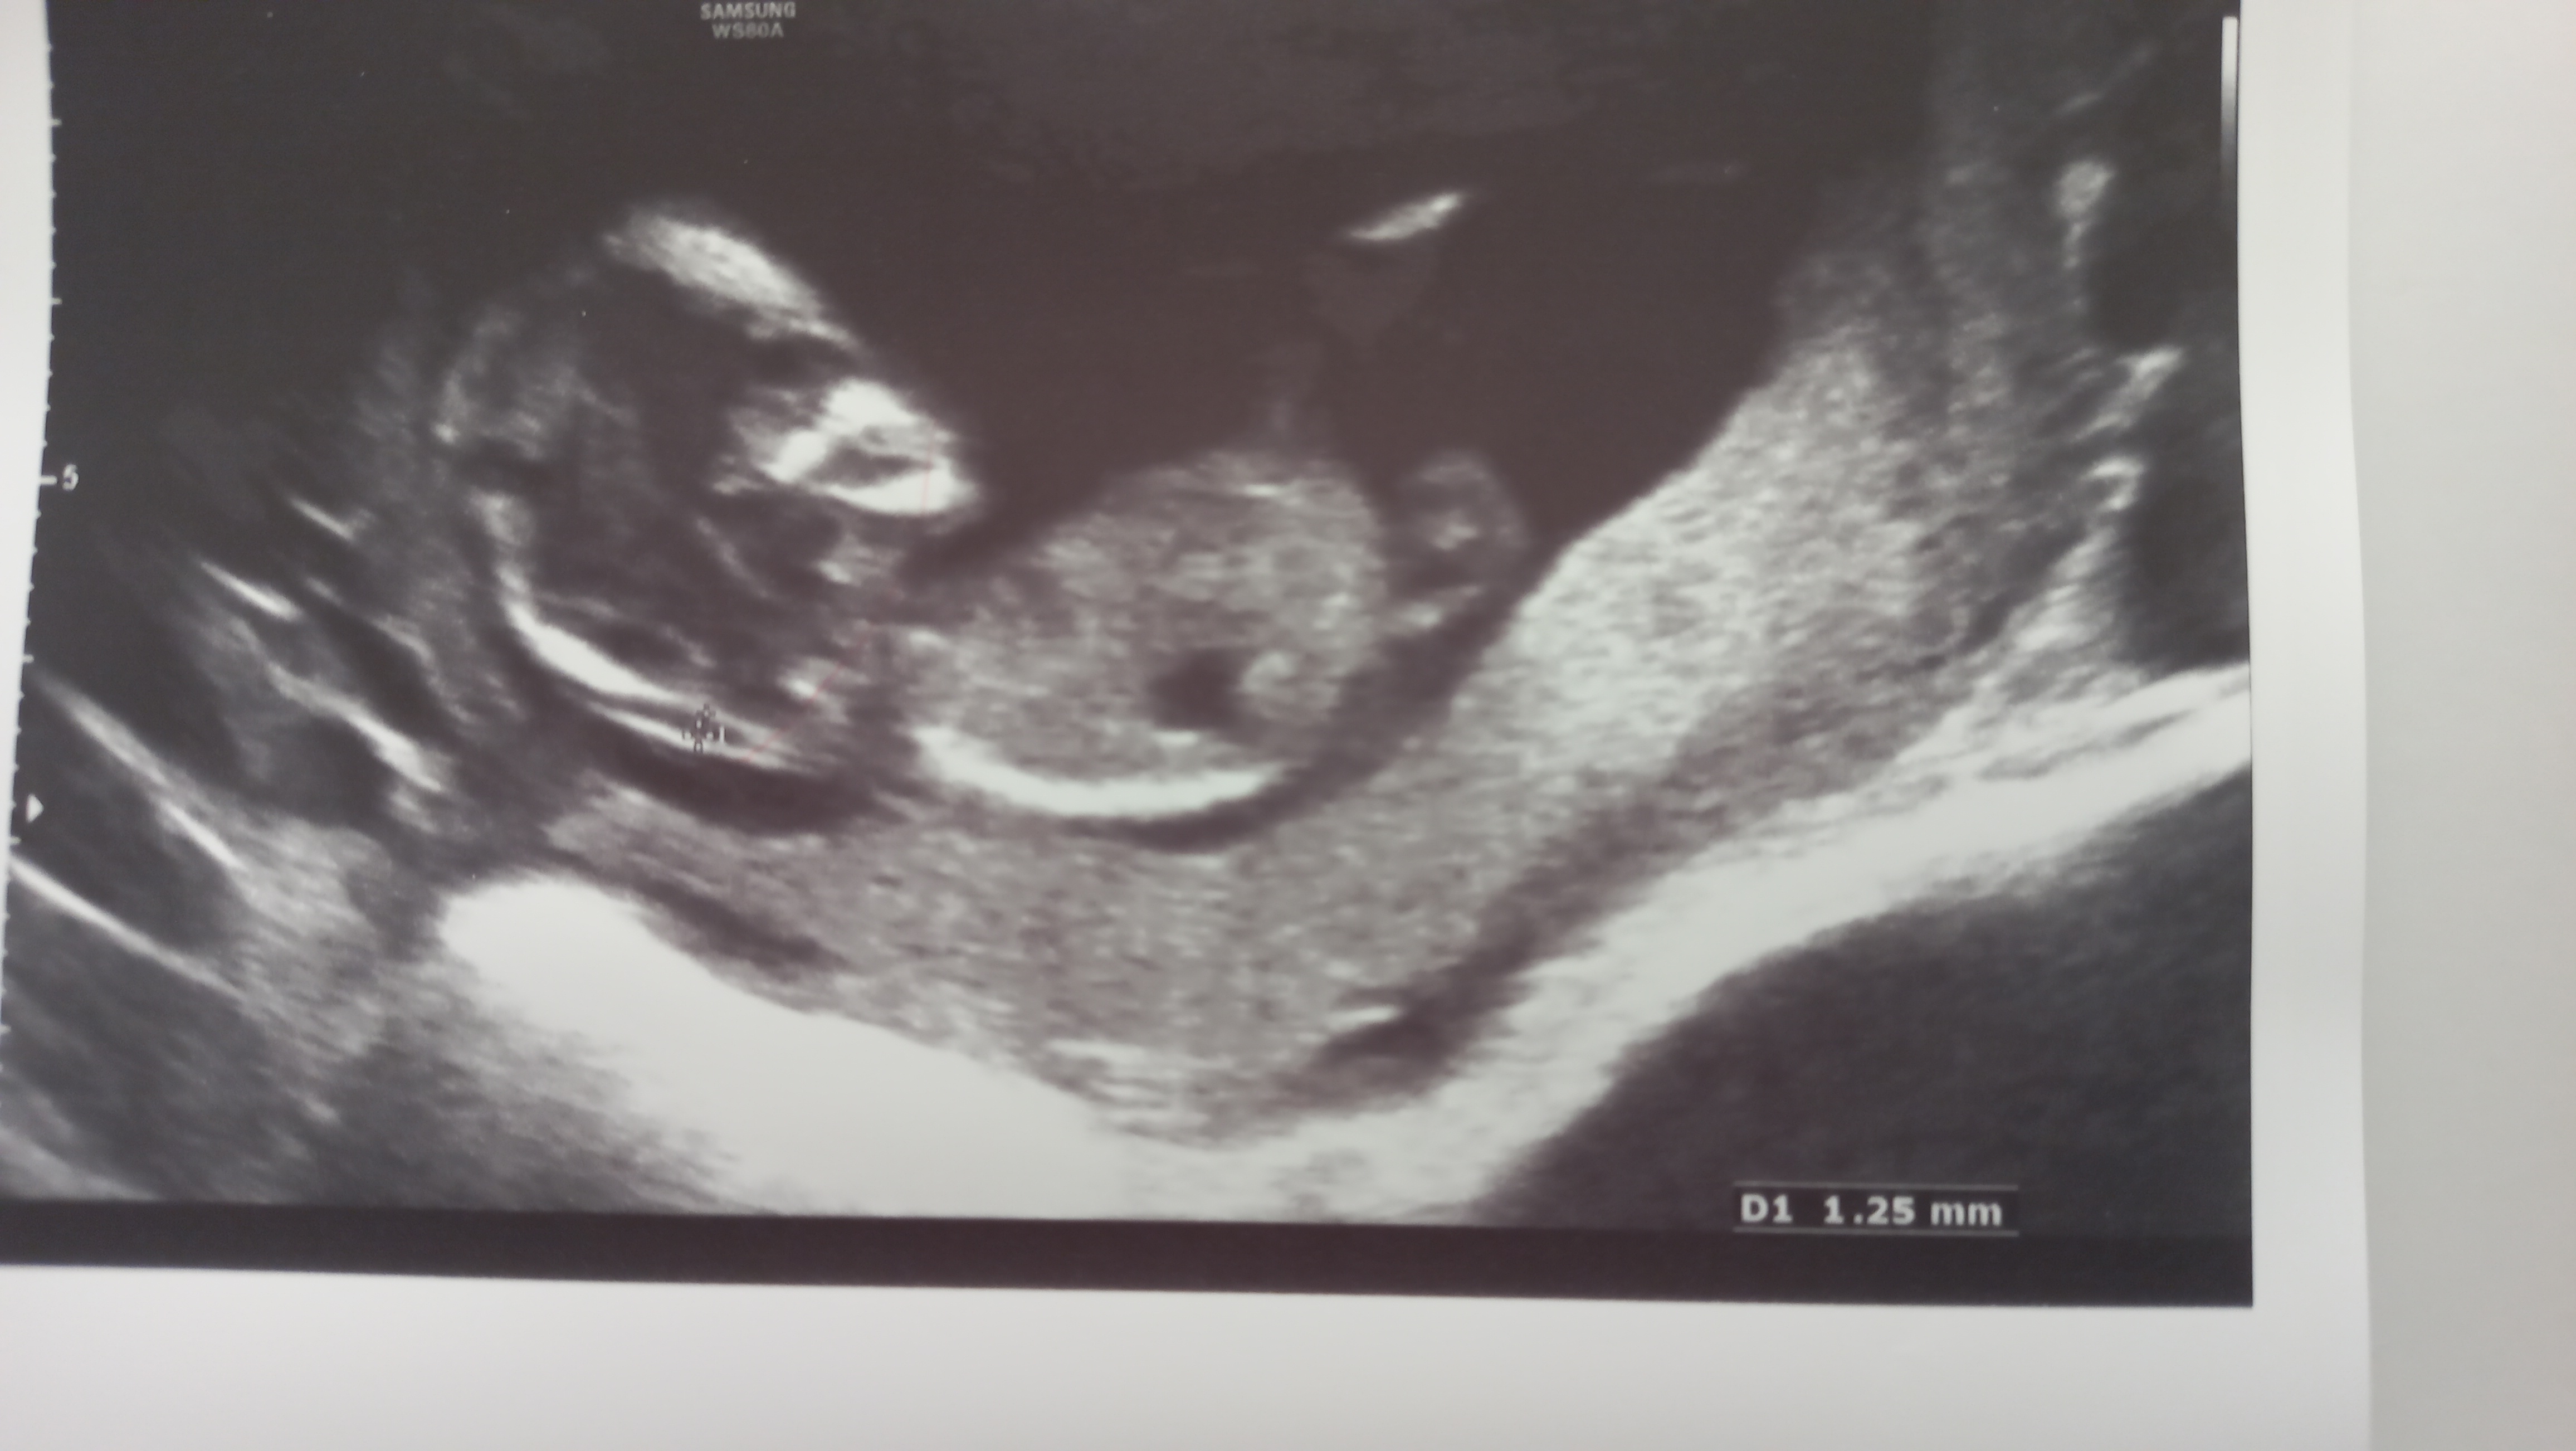

عکس های سونوگرافی در بارداری

من رفتم سونوی ان تی خیلی عکس قشنگی بهم داد قشنگ بچه توش مشخص بود. می خوام بذارم تو آلبومش.

سوالم اینه که سونوگرافی های ساده هم تو بارداری از این هفته به بعد عکس های خوب اینطوری میدن یا فقط غربالگری های ان تی و آنومالی اینجورین؟

آهان نمیدونم شاید بچه خوب قرار نگرفته بوده. من عکسای آنومالی رو تو اینترنت دیدم بعضیاش قشنگ بود